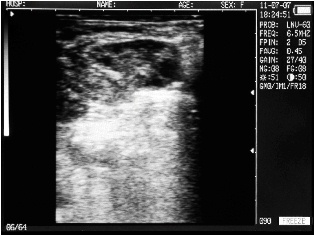

Ultrasound images of cows reproductive system, generated by a scanner Sonovet with rectal linear transducer.

Hypovarianism cow